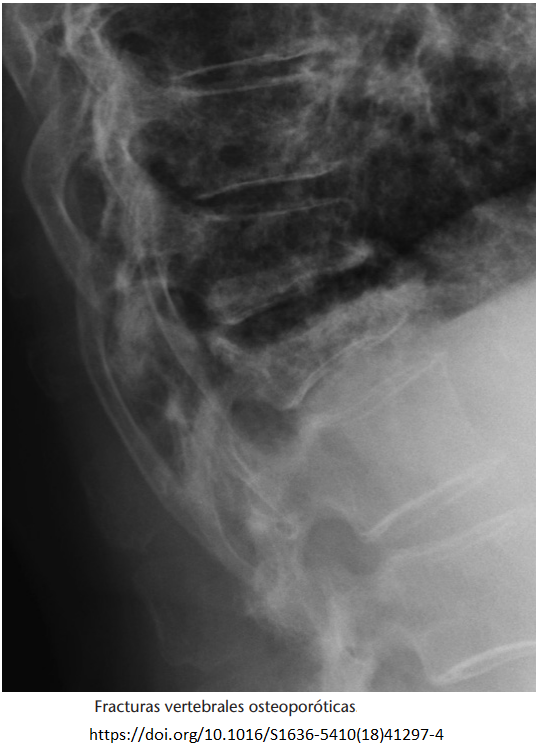

- Fractura vertebral (postraumática, osteoporótica).